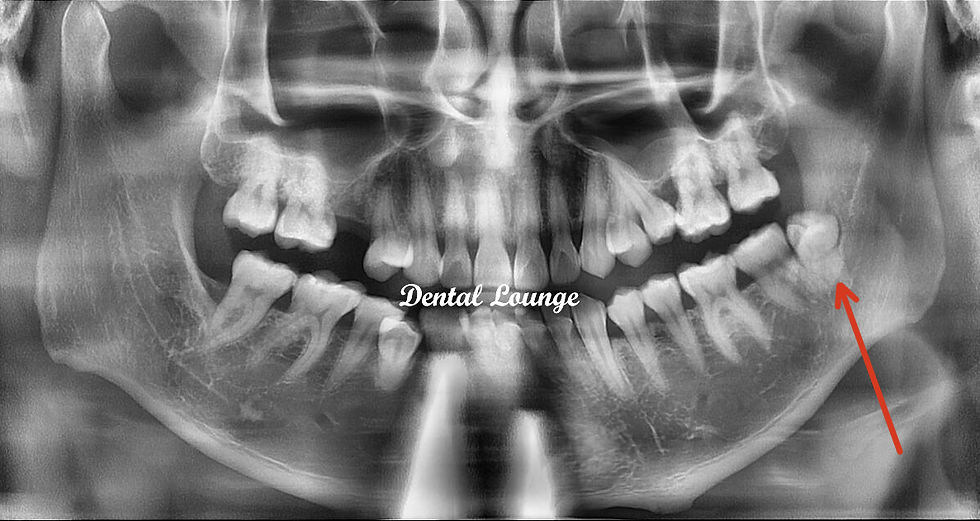

Surgical Removal of Impacted #38

Pain on distal of #37, partially erupted and impacted #38 with pericoronitis.

Partial eruption and impaction of #38

Pre-operative CBCT shows #38 is distolingually tilted and impacted with a bony coronoid

IDN plotted lingual to #38 roots and passes between the roots

Curved roots of #38